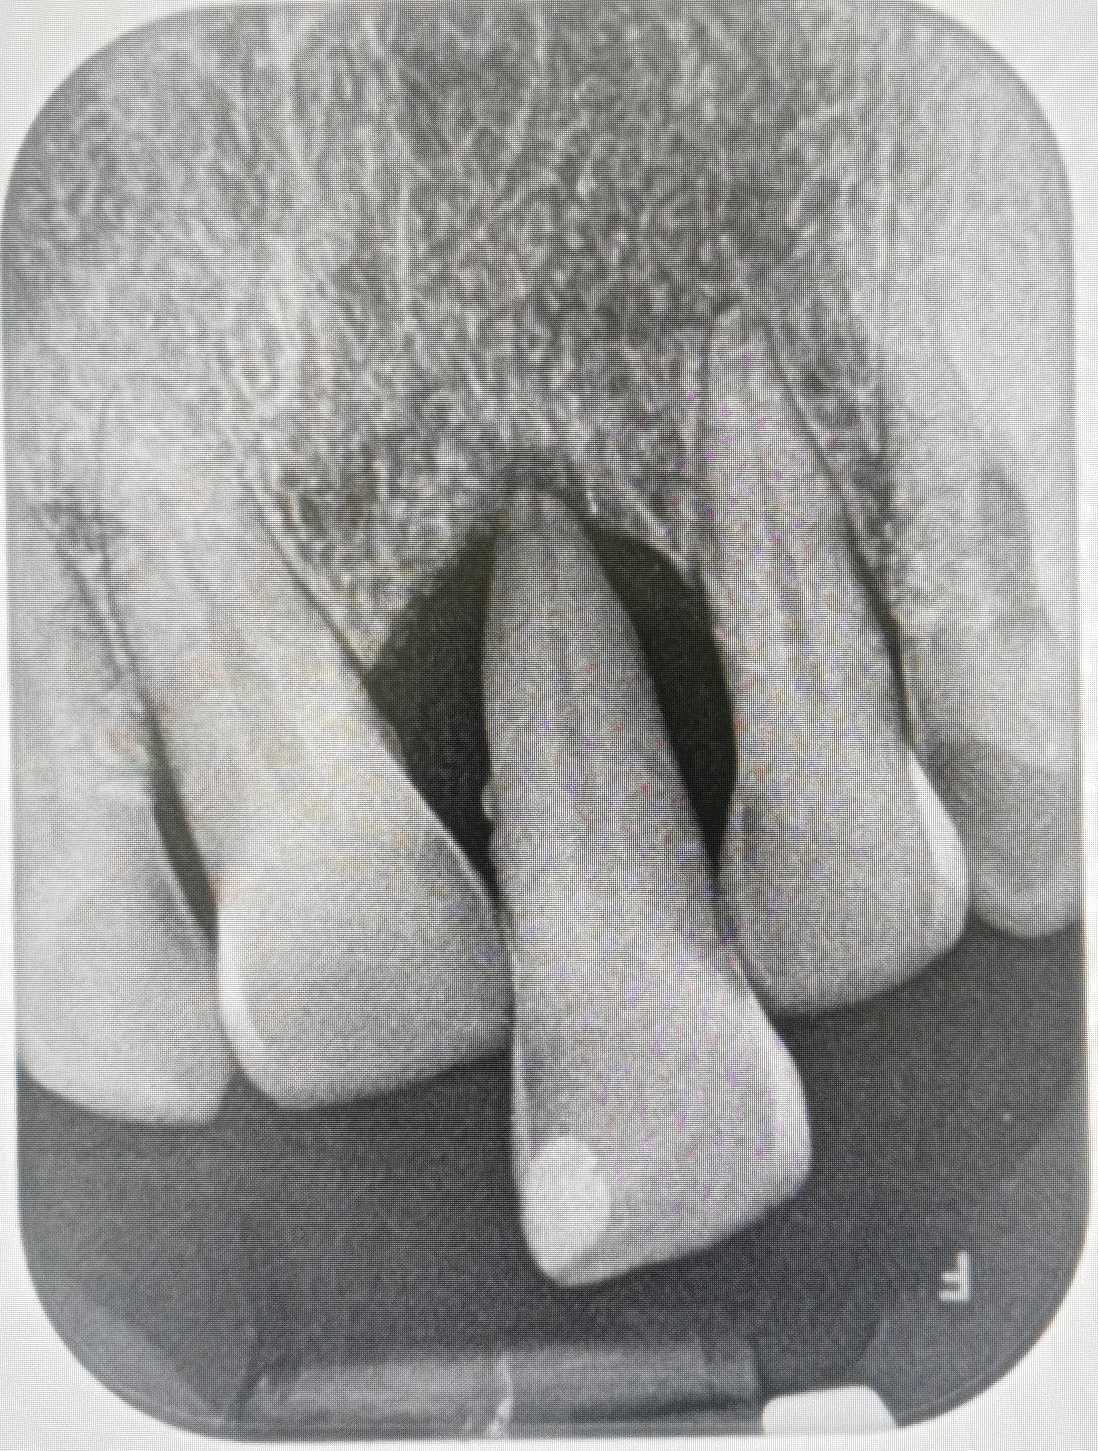

Immediate denture

ในกรณีฟันหน้าที่มีความจำเป็นต้องถอนฟัน สามารถถอนฟันแล้วใส่ฟันปลอมทดแทนได้เลย ฟันปลอมชนิดนี้เรียกว่า immediate denture ข้อดีของการทำฟันปลอมชนิดนี้คือสามารถเติมเต็มความสวยงามให้ผู้ป่วยได้ทันทีหลังถอนฟัน แต่ฟันปลอมชนิดนี้ก็มีข้อเสียเช่นเดียวกัน เช่นอาจเกิดช่องว่างระหว่างฐานฟันปลอมกับสันเหงือกเมื่อแผลถอนฟันหายเต็มที่แล้ว